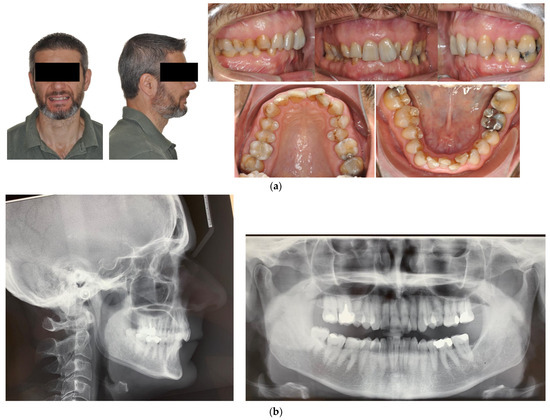

- Case 3: Class II subdivision with deep bite

4.3. Case 3: Class II Subdivision with a Deep Bite